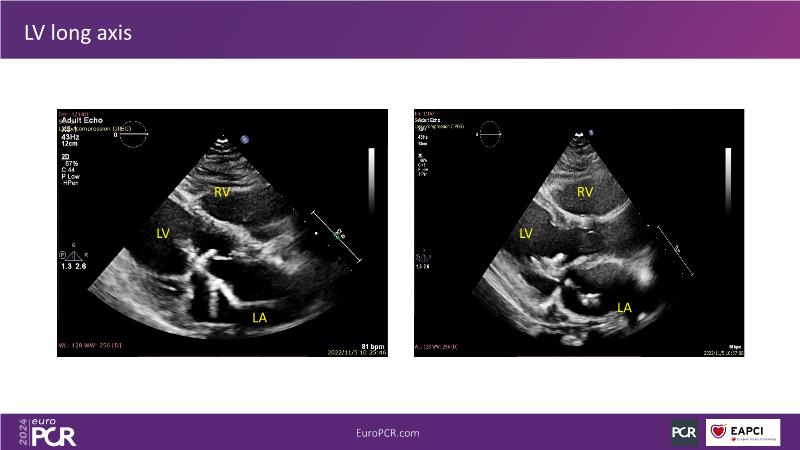

Watch this session to gain insights into the clinical evidence of mitral TEER therapy for the Asian population, learn techniques for implanting a MitraClip in patients with challenging anatomy, and understand how to use the four clip sizes for optimal outcomes. The session also covers educational aspects of clipping in dextrocardia, the benefits of reserve bending of the transseptal needle for tenting and puncture, new steering maneuvers for dextrocardia patients, and the importance of understanding anatomy and collaborating closely with the echo team for success.